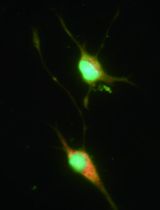

The human endometrium is the inner most mucosal layer of the uterus. It consists of a columnar epithelium and basal stromal layer that undergoes cyclical regeneration, growth and transformation in response to circulating hormones. The differentiation of the endometrial lining into a glandular secretory phenotype provides a hospitable environment for blastocyst implantation and successful pregnancy. In the absence of pregnancy this layer is shed, leading to menstruation. The isolation and culture of cells from human endometrial biopsies allows for in vitro functional assessment and the study of cell characteristics in relation to patient outcomes. The isolation and culture of endometrial cells is an invaluable research model to investigate many aspects of gynaecological and obstetrical medicine including infertility, implantation failure, recurrent miscarriage and menstrual disorders. Whole human endometrial biopsies contain human endometrial stromal cells (HESCs), luminal and glandular endometrial epithelial cells (HEECs), red blood cells and a mixed population of immune cells. HESCs can be easily and inexpensively isolated from whole biopsies and actively proliferate in culture for up to 5 passages without significant change in their growth dynamics. This provides a large window of opportunity for experimental analysis. Furthermore, within dissociated HESCs there is a sub-population of perivascular progenitor mesenchymal stem-like cells that can be isolated using the perivascular-specific antigen SUSD2 and its cognate antibody W5C5. Here we provide in detail an updated and expanded protocol from those published previously (Masuda et al., 2012; Chen and Roan, 2015) to describe steps in isolating and culturing different cell types from whole human endometrium. We provide further information on biopsy collection, detailed protocols for isolation of progenitor cells and additional procedures to increase epithelial cell yield and culturing efficiency.